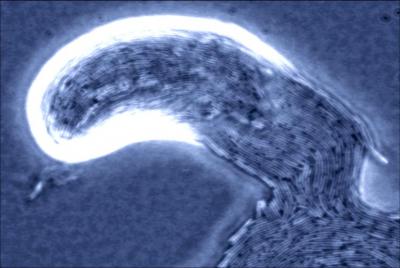

P. mirabilis cells can stick together on catheter surfaces where they form highly organized communities called biofilms. As the bacterium breaks down urea (using the enzyme urease) it causes the pH of urine to rise, leading to the formation of insoluble crystals which become trapped in the growing biofilm. The crystalline deposits can form a crust on the catheter and may eventually block urine flow from the bladder. If unnoticed, catheter blockage can lead to kidney and bloodstream infections, which ultimately may result in potentially fatal septic shock.

The team is identifying genes involved in P. mirabilis biofilm formation, and assessing their contribution to catheter blockage. The results show that biofilm-forming ability may be less important to catheter blockage than previously thought, and suggest that inhibiting the rise in urinary pH is a primary target for preventing catheter blockage. Nina Holling who is carrying out the research said, "In our experiments we have found biofilm-forming ability not to be the most important factor in catheter blockage. Although biofilm formation does play a role, the ability of P. mirabilis to increase urinary pH and form crystals seems to compensate for deficiencies in biofilm formation. However, much more work is required to fully understand the progression of these infections and biofilm formation may be more important in the early stages of infection."